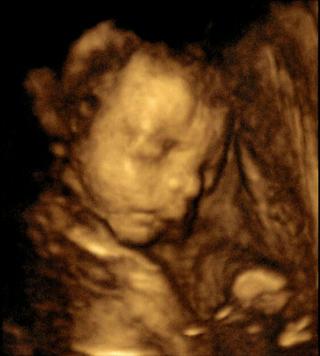

Jsme zpět z 4D - byl to fakt zážitek, i když prcek moc nespolupracoval - pořád měl ručičky před obličejem a nakonec si tam pro jistotu strčil i obě nožičky 😉 Aktivní jinak moc není, celou dobu vydržel víceméně v jedné poloze, žádný artista. Opět jsme si potvrdili, že to bude chlapeček, všichni jsme viděli pindíka a kouličky 😉 Jinak je podobný na manželovu rodinu (tlusté rty a pršáček), obvod hlavičky 23cm, váha cca 1025g, odpovídá o jeden den TP (26+6). Bylo moc hezký vidět mimčo, jak se mu uvnitř daří, jak je v pohodě. Byl moc roztomilej - přikládám fotku.

@bugee ten je krááááásnej!!!🙂to je drobeček roztomiloučkej!!no úplně k umazlení 🙂 🙂 🙂 🙂 🙂

@bugee krásná fotečka 🙂 !!! to je ťutík roztomilej ...máte podobný snímeček jako my - jsou tam v pohodě ty naše miminka, viď? I když ta naše cácorka cvičí podobně jako u @jajinka28 . Ale naštěstí v noci je hodná. Přes den se mele a vrtí konstantně, i teď když ležím, ale v noci je klidná. Probouzí se ráno v 8....to je vždycky legrace, jak se začne napřed protahovat a pak následuje pořádná rozcvička, že břicho skáče na všechny strany 😀